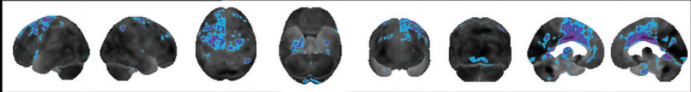

corticobasal degeneration